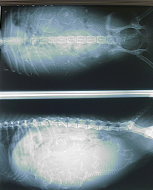

上からみたレントゲンと

横からみたレントゲン

病院でレントゲン写真を撮っていただきました。

産道と胎児の頭の大きさチェックです。普通分娩が可能であるかの確認のためです(産道の幅より頭が極端に大きいと帝王切開の確率が増えます)。

なんと4匹の胎児が順調に育っていました。よんひき!・・・・・・・・・・・・。

上から撮ったレントゲンです。中央がまめの背骨。左右に小さい4匹分の背骨と頭が見えます。右の子宮に2匹、左の子宮に2匹です。

横から撮ったレントゲンです。右がお尻のあるほうです。

2匹(産道側)が逆子です。そのため4匹が頭をくっつけている状態でお腹におさまっています。お腹の下の方に4匹の頭が重なっているのがわかりますか?

なんだか、4匹でひそひそ相談しているように見えます(笑)。

産道より胎児の頭の方が小さいので、今週中に生まれるとすれば順調な出産になるそうです。

4匹もいるので、あまりおおきく育っていないようです。産むのは楽かも。